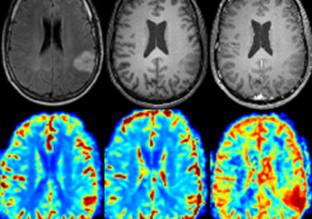

Will the radiology of the future come from machine learning? That is the view of Inserm and Inria researchers working in collaboration at the Université Grenoble Alpes who have developed a program able to localize and diagnose various types of brain tumors via MRI image analysis. These analyses have produced highly reliable results, with tumor localizations and tumor-type diagnoses accurate in 100% and over 90% of cases, respectively. This...